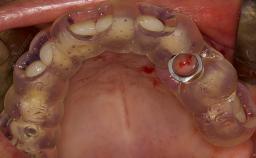

• intraoperative complications of lateral window sinus floor elevation

• intraoperative complications of transcrestal sinus floor elevation

• postoperative complications of sinus floor elevation